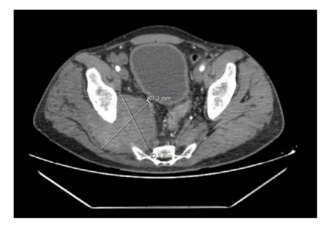

The authors report hybrid management of 2 cases of post-traumatic symptomatic pseudoaneurysms of the gluteal arteries in 2 young male patients.